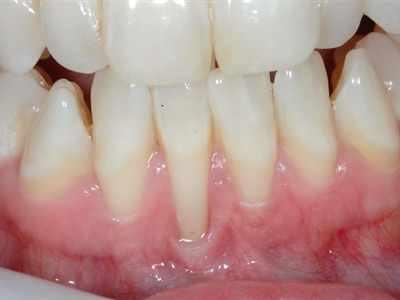

牙龈退缩多颗牙齿牙龈萎缩牙根暴露图

牙龈退缩患者的上下排大多数牙根出现轻度暴露,外漏的牙体变长,牙根处的牙龈肉体泛白,有轻微的肿胀。牙齿敏感,会因进食而出现不适。